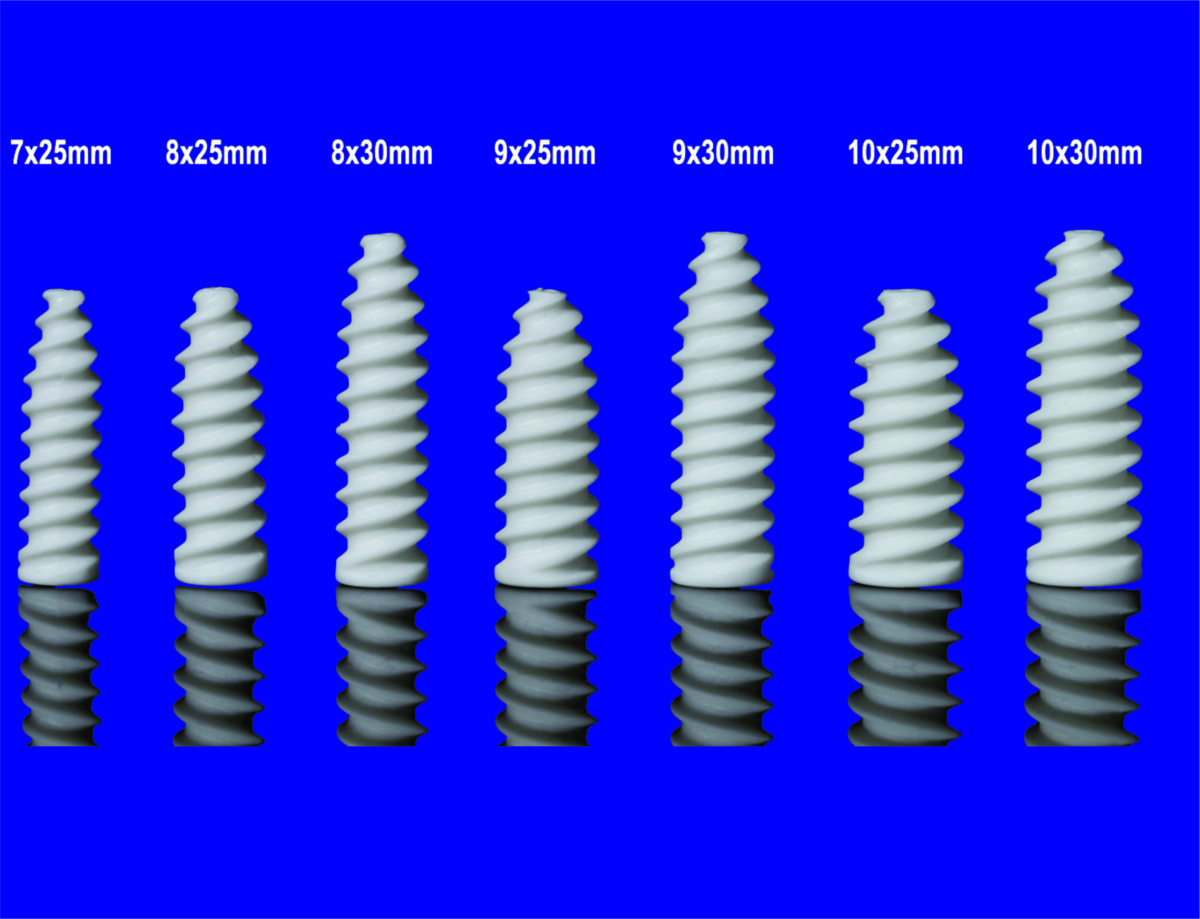

PARAFUSO INTERFERÊNCIA MASTERTECK EM PEEK

Matéria Prima: PEEK (Poli-Éter-Éter-Cetona com adição de 6% de Sulfato de Bário, para uso medicinal), termoplástico biocompatível, especifico para uso médico.

Descrição

É um parafuso canulado, de uso único, produzido em polímero termoplástico a base de Poli-Eter-Eter-Cetona, extremamente biocompatível, com adição de 6% de sulfato de bário em sua composição que facilita a sua visualização em exames de imagem.

São indicados para utilização em qualquer situação de fixação de estruturas não ficando somente ligados a fixação de ligamentos cruzados do joelho. Assim sendo possível sua utilização diversificada.